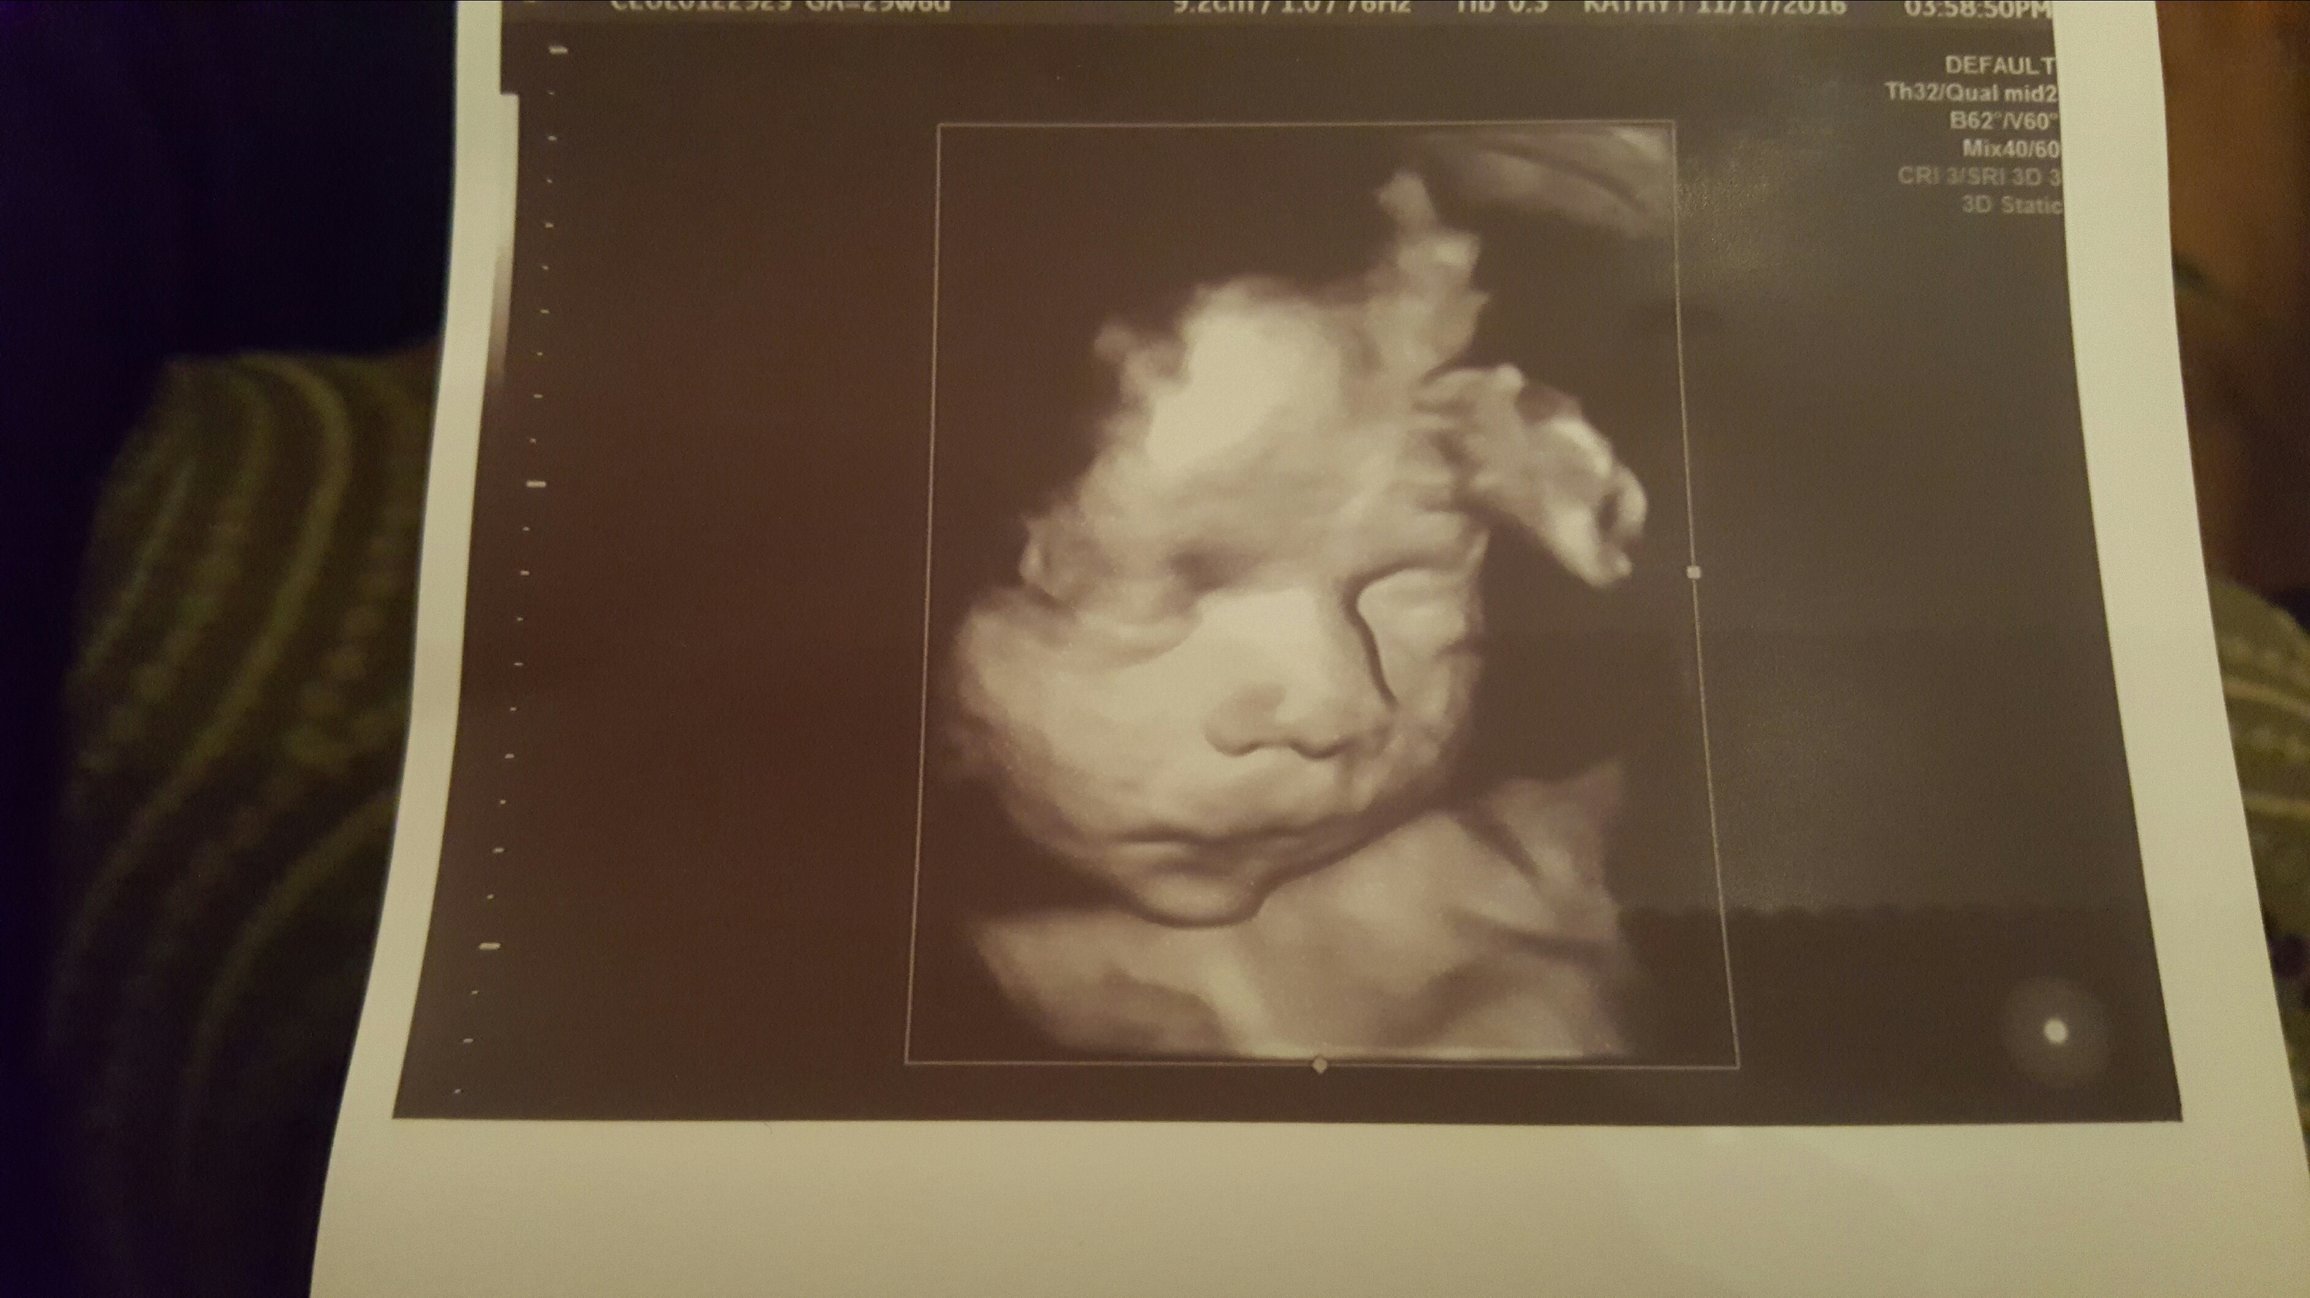

@dragonfaerie I completely missed your pictures, they didn't load before when I was writing my previous comment. I love the 3D ultrasound and the nursery is coming together so nicely! I wish I had a talent to do stuff like that.